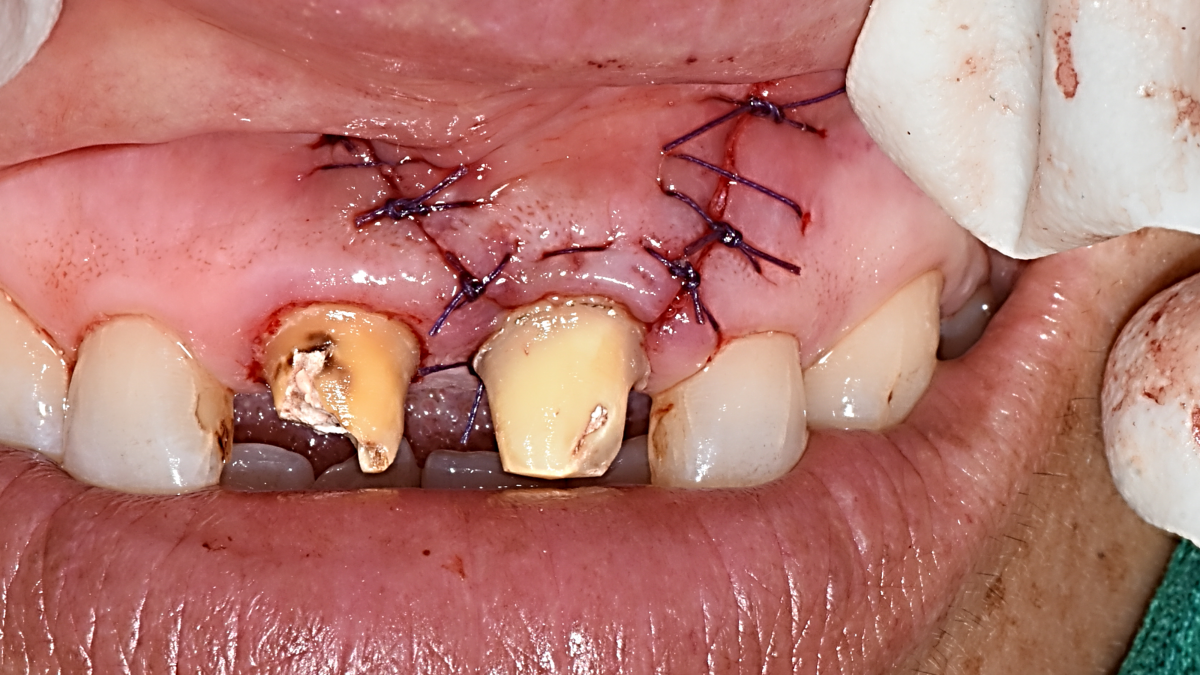

Apicorctomy /central incisor /GBR ; 6-year follow up.

<CJ SBN> Apicorctomy /central incisor /GBR ; 6-year follow up.